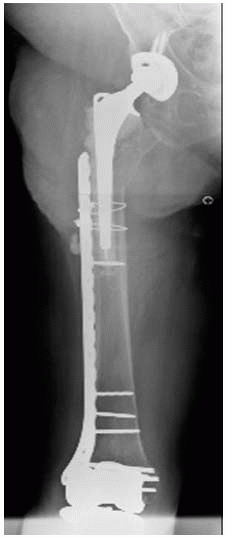

![]() |

FIGURE 21-10 Proximal femoral allograft/revision stem composite for treatment of Vancouver type B3 periprosthetic femur fractures. A. The allograft/prosthesis composite is inserted into the native host distal femoral segment. B.

Any remaining proximal sleeves of host bone with soft tissue attachments are secured to the allograft and across the allografthost junction. C. The greater trochanter is separately attached to the allograft. |

FIGURE 21-11 A.

Ill-advised treatment of a Vancouver type C femur fracture distal to a hip arthroplasty stem. The nail eroded through the anterior cortex and the fracture developed nonunion. This was treated with nail removal, ORIF with a lateral plate, autologus bone graft to stimulate nonunion healing, and an anterior strut graft to restore bone stock (B,C). |